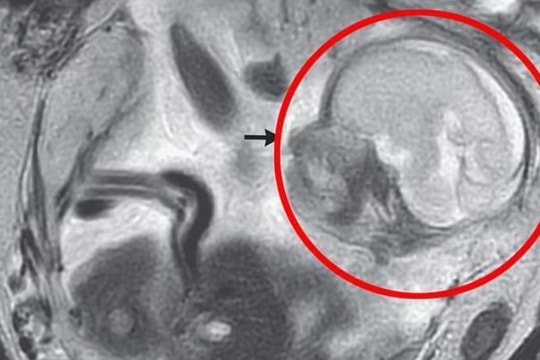

Mổ sinh, phát hiện u quái giống hình hài 1 thai nhi

Sau khi mổ lấy thai nhi, các bác sĩ phát hiện vùng tiểu khung bên phải của bệnh nhân có khối u quái kích thước 7x13cm dính cắm sâu vào đoạn eo tử cung, mặt sau bàng quang, mạc nối lớn, các quai ruột và dính vào thành bụng sau.